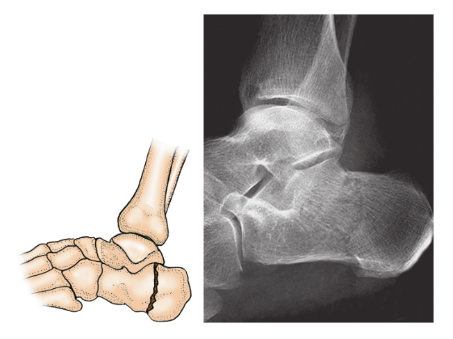

3、跟骨体骨折:

跟骨体骨折:跟骨受到纵向暴力引起,骨折线常常呈纵行或者斜行经过后距下关节面的后方,形成简单或者粉碎骨折(图8)。

图8 跟骨体骨折